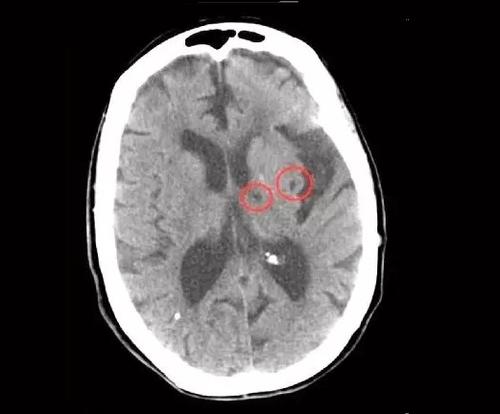

3,腔隙性脑梗塞,通常为1、5公分以下的较小的梗塞灶。是较细的穿支血管发生堵塞,梗塞后死亡的脑细胞被巨噬细胞吞噬,形成了一些空腔,所有就叫腔隙性脑梗塞。其临床症状较轻,往往被基础病症所掩盖,只是体检时被CT发现。